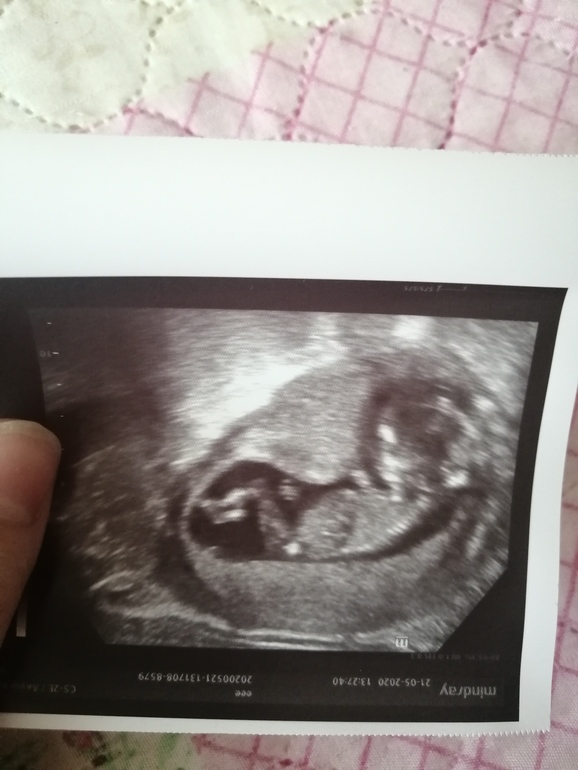

Вот девочка 14 недель)